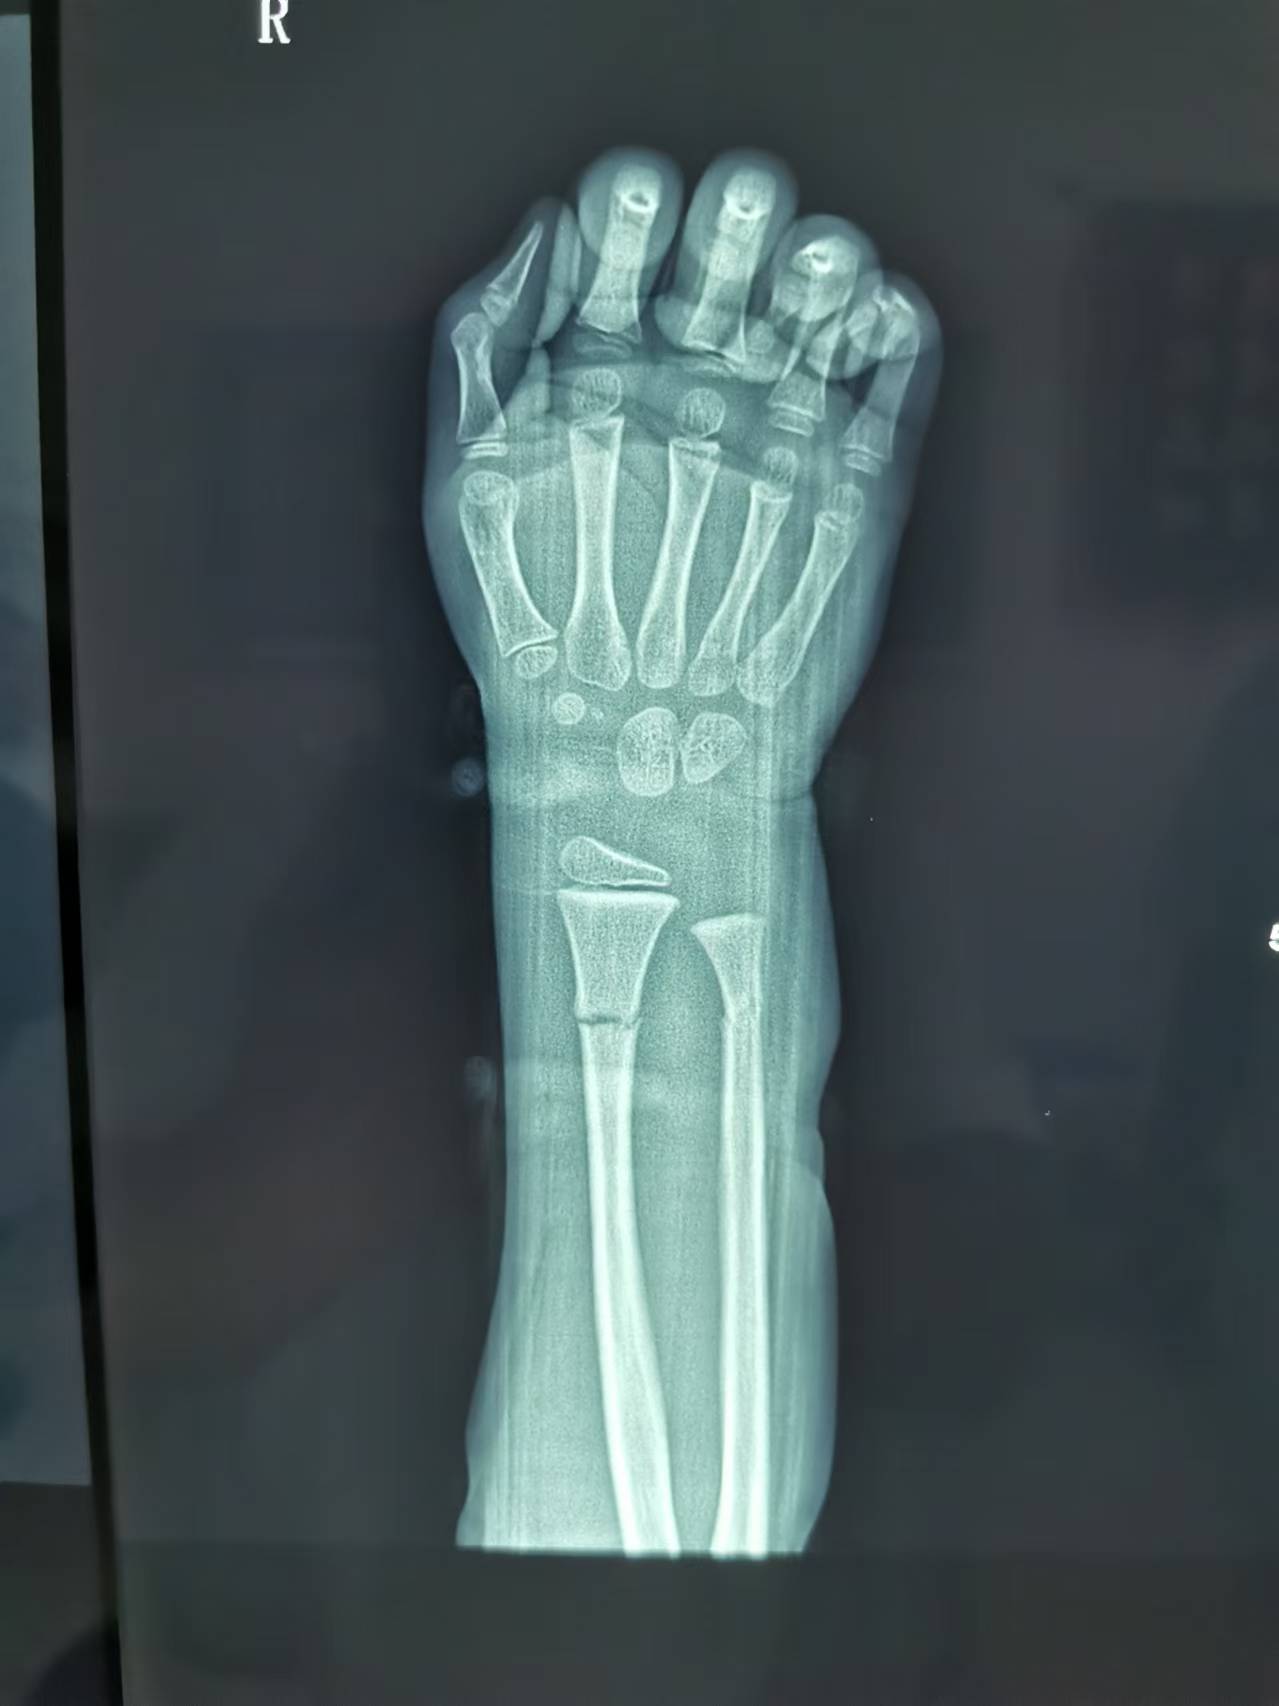

首页 > 张恒云工作室 > 影像资料 一